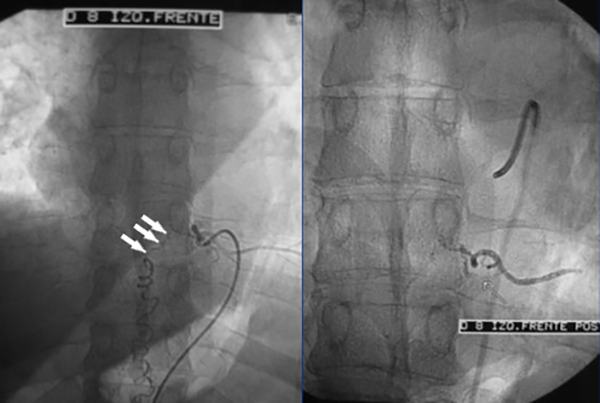

Figura 9: Caso #2. RMN preoperatoria en secuencia T2, a la izquierda se observa en el corte sagital el característico edema centromedular multisegmentario. A la derecha se aprecia, en el corte axial, los múltiples vasos perimedulares y el edema centromedular.

Figura 10: Caso #2. ADM preoperatoria en AP y OAI. La misma arteria radiculomedular D 7 izq. (1) da origen a la arteria de Adamkiewicz (4) y a la FDAVE (2); pie de vena de drenaje (3); horquilla de la arteria de Adamkiewicz (5); arteria espinal anterior (6) y vena espinal posterior (7).